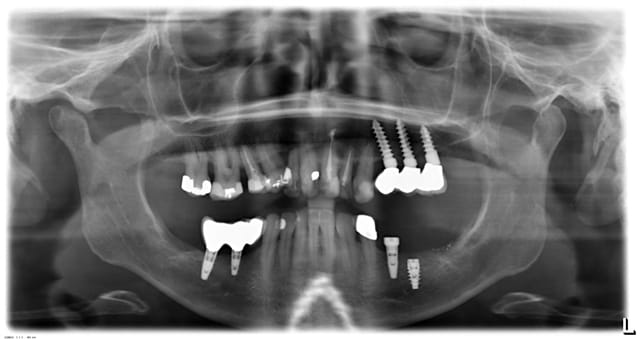

J'ai posé un Nobel Acitve en 36 avec extraction implantation immédiate en décembre 2014. J'ai serré la vis de cicatrisation à la main comme d'habitude.

Aujourd'hui 2e temps chirurgical pour dégager la vis de cictrisation et la vis est recouverte presque entièrement par de l'os.

j'ai essayé avec les trépans qui sont dans la boîte chir chez Nobel, mais je n'y arrive pas.

J'avais essayé avec un gratte os Buser Hu friedy, ce qui dégagaeait la vis. Puis je suis passé un peu autour avec une Zekrya sans toucher la vis ou l'implant, mais j'arrive pas à dévisser. Je pense que j'ai pas assez dégagé l'os et ça coince encore à un endroit, je ne voulais pas trop forcer non plus pour dévisser par peur d'abîmer la connectique ou le pas de vis.